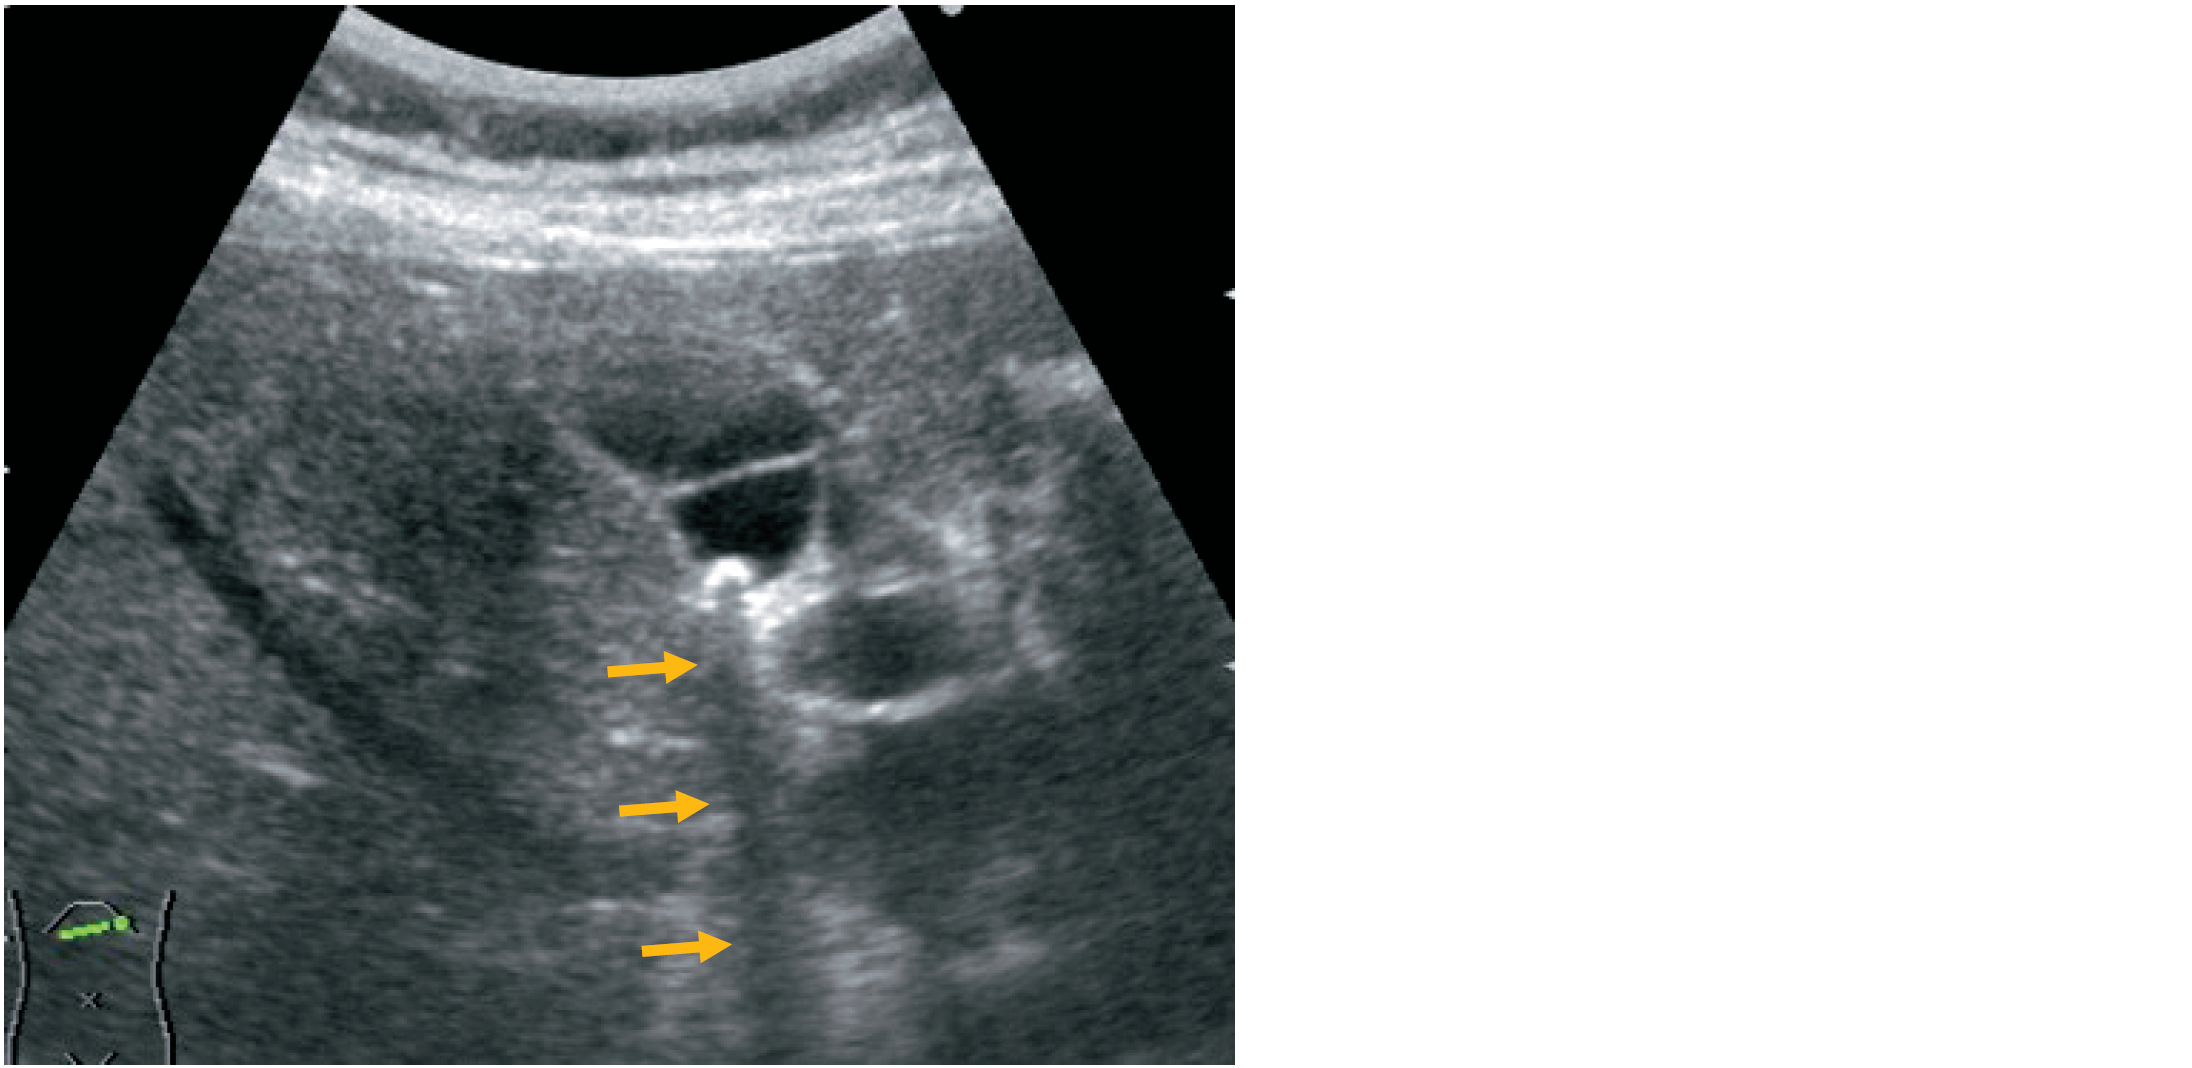

心窩部斜走査による超音波像を示す。

矢印で示すのはどれか。

1. 音響陰影

2. 外側陰影

3. 鏡面現象

4. 多重反射

5. 後方エコー増強